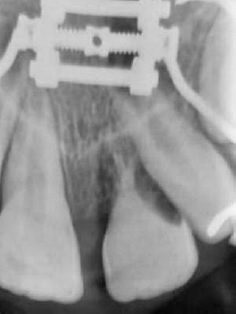

The avulsed tooth had an intact crown and a two-thirds formed root with a wide-opened apex. The dentist seized the tooth from the saline solution, holding it by the crown and not touching the root surface, and gently rinsed it with 0.12% chlorhexidine. Local anesthesia (2% lidocaine hydrochloride with 1:100000 epinephrine vasoconstrictor) was administered through labial and palatal infiltration in the affected area. The alveolar socket was gently rinsed with saline solution. The avulsed tooth was restored into the socket with slight digital pressure, ensuring its correct position. The replanted tooth was splinted with a 0.4-mm stainless steel orthodontic wire and brackets, placed on the left deciduous canine (63), the right maxillary central incisor (11), and the right deciduous canine (53) (Figure 2). The brackets were fixed away from the gingival tissues and proximal areas after etching the crown surfasse with 37% phosphoric acid for 20 seconds, rinsing with water, air drying, and applying a bonding agent and a composite resin.

The dental apex was wide open, and the crown changed color slightly. The dentist checked the occlusion and prescribed oral anti-inflammatory and antibiotic medications: ibuprofen 100 mg/mL, 20 drops twice daily, and amoxicillin 400 mg/potassium clavulanate 57 mg per 5 mL, twice daily for ten days. Homeopathic remedies were also prescribed: Symphytum CH5 associated with Marigold CH3 30 mL 5% alcohol, eight drops thrice daily for 30 days. The patient had recently received an unnecessary tetanus booster vaccine. He was advised to maintain a soft diet for 15 days and use a soft-bristled toothbrush and 0.12% chlorhexidine mouth rinse twice daily for oral hygiene maintenance.

After one week, periapical radiography revealed the correct positioning of the tooth and a regular aspect of the root surfasse (Figure 3). Fifteen days after replantation, the splint was removed.

Figure 3 Periapical radiograph one week after the trauma, with the left maxillary central incisor (21) showing a regular root surface aspect.